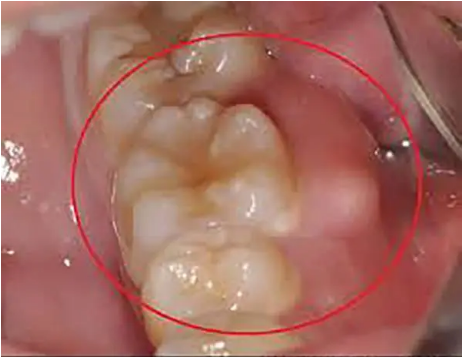

牙周脓肿

医师行洁治术或刮治术时动作粗暴,将牙石碎片及细菌推入牙周袋深部组织;或者深牙周袋内的牙石刮治不彻底,牙周袋浅层牙石被去除。

而牙周袋深部牙石未完全去除,导致牙周袋袋口紧缩,袋底炎症向深部结缔组织扩散,而脓液无法向袋内排除时,可形成袋壁软组织内的脓肿;单纯应用全身消炎收敛药物、未结合机械法清除菌斑、牙石,导致牙周袋口的牙龈反应性收缩,深牙周袋引流不畅,易形成牙周脓肿。

这种牙周脓肿应与牙根纵裂、根管或髓室底侧穿、全身系统疾病(如糖尿病)等导致的牙周脓肿相鉴别。